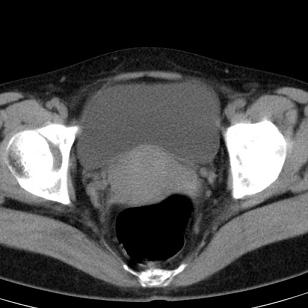

标题: CT19559:子宫及附件正常吗?

女,35岁,反复下腹部隐痛数月。

感觉上,子宫好象大了点

如果未孕,子宫体稍大,宫腔增宽,附件区未见异常密度影,还是建议结合b超检查为好,ct平扫对妇科没有优势。

子宫弥漫性等密度肿大,宫腔内缘见结节影突入腔内,子宫内膜异位可能